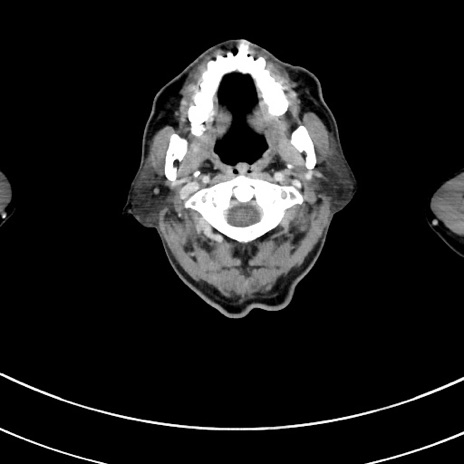

症例8(横断像)

【症例】 60歳代男性

【主訴】 黒色吐物

【現病歴】 4日前から嘔気自覚、2日前の朝食後にも嘔気あり、自分で手で嘔吐反射起こし嘔吐したところ血が混ざっていたため受診。

【既往歴】 5年前汎発性腹膜炎を伴う急性虫垂炎で手術、高血圧、前立腺肥大症、高脂血症

【身体所見】 腹部正中に手術癩痕あり 腹部平坦・軟圧痛なし膨満感あり

【データ】WBC 8400、CRP 4.54